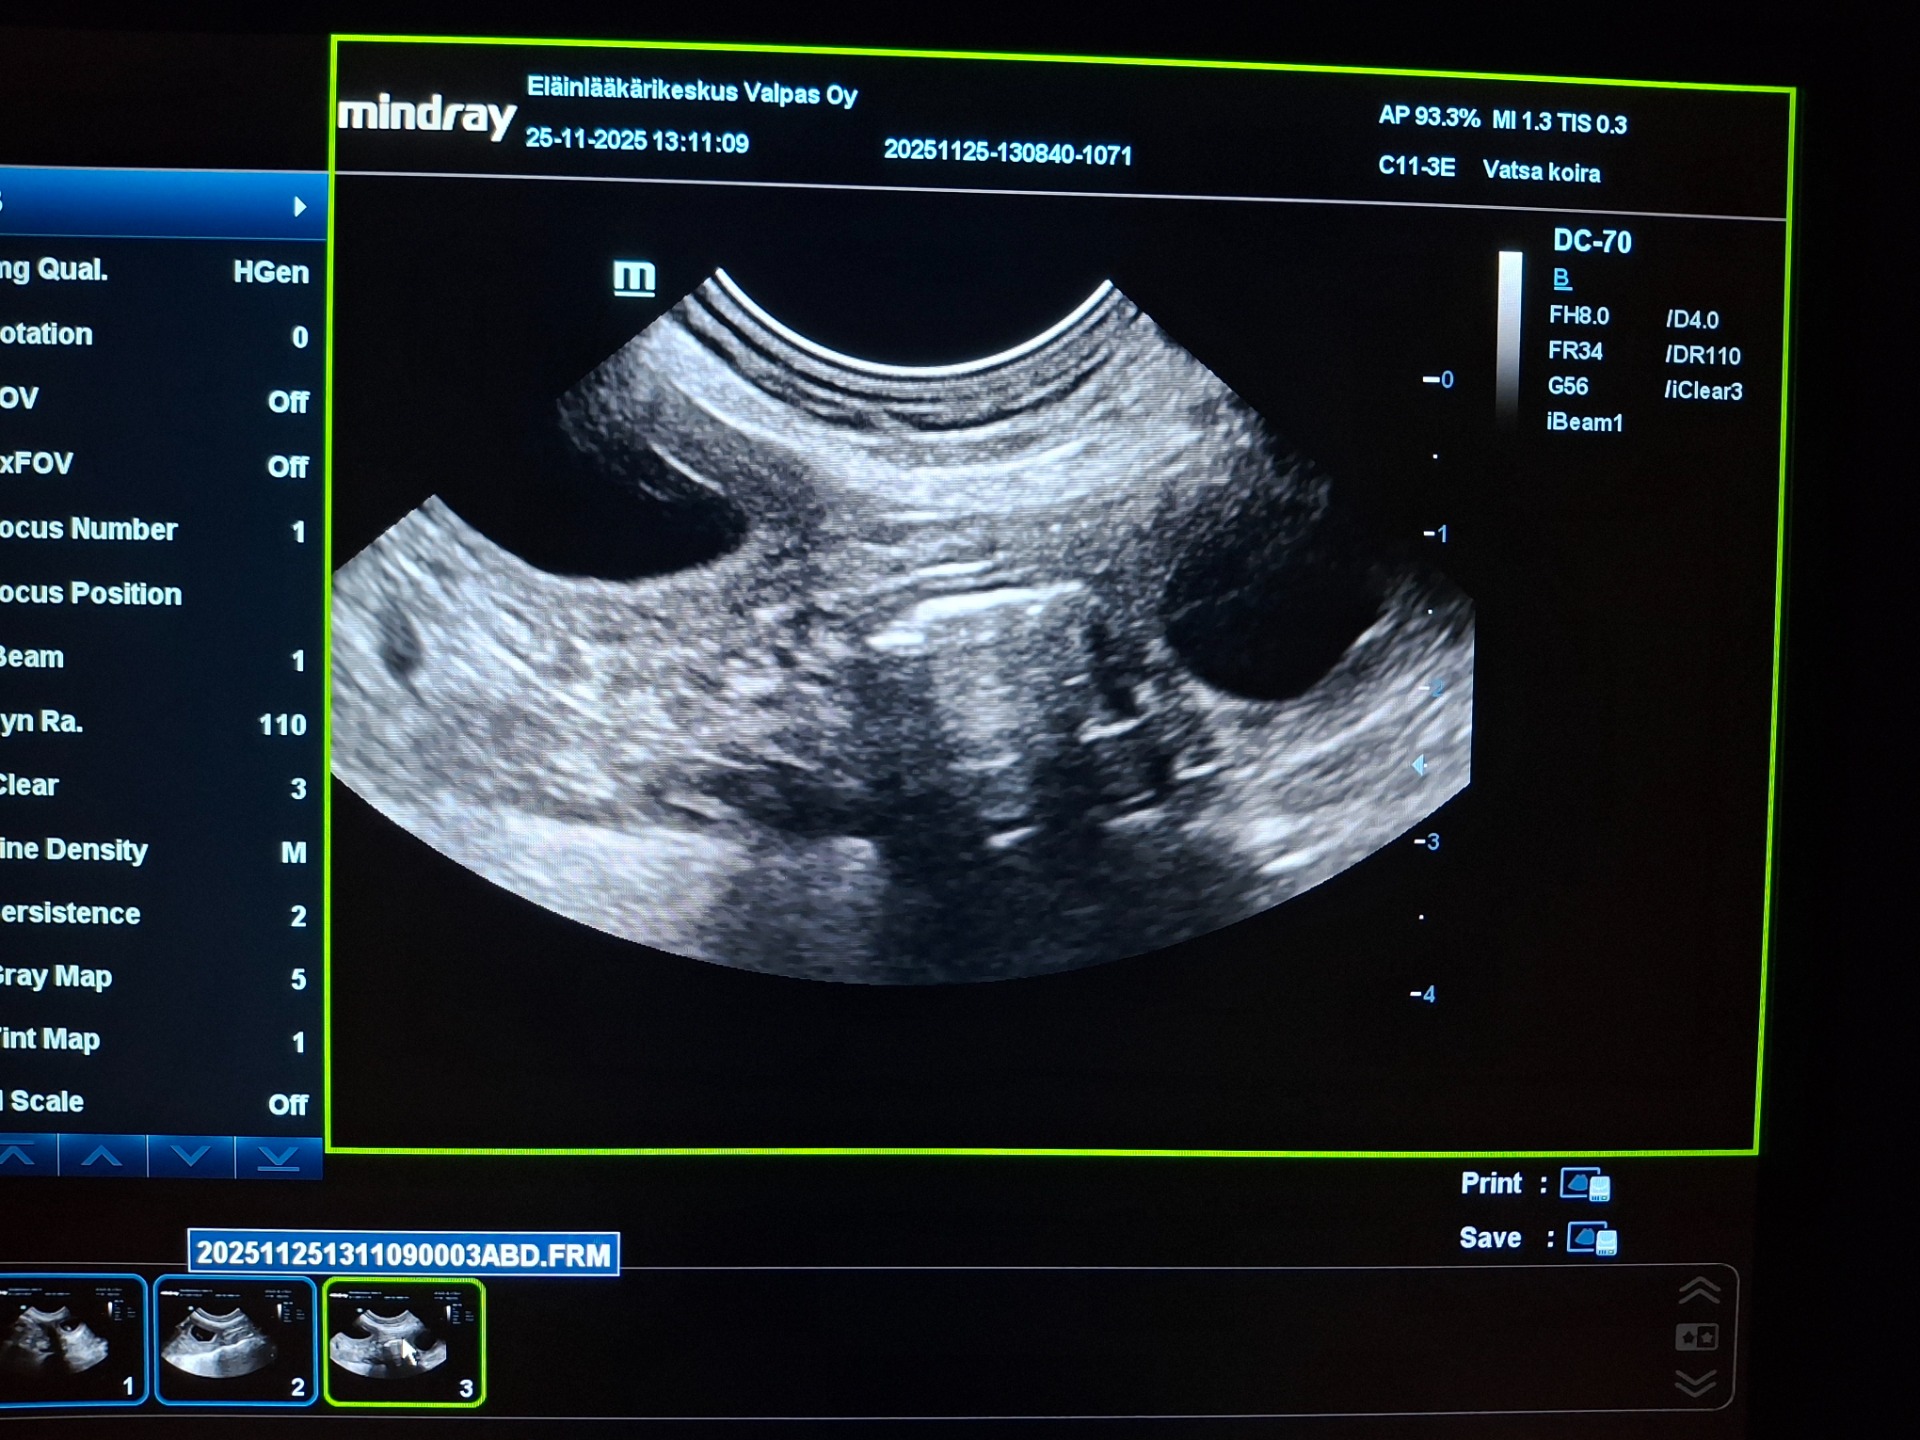

25.11.2025

Lola on ultrattu ja 2 pentua on tulossa varmuudella❤️ Pennut syntyvät joulukuun loppupuolella🥰